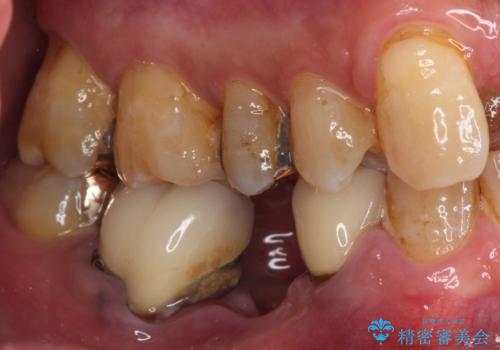

- 下顎両側の欠損と上顎前歯のデコボコを気にして来院された患者様です。

奥歯に欠損が多く、矯正治療はやや難航することが予想されますが、患者様の希望もあり、上顎左右小臼歯を1本ずつ抜歯し、ワイヤー装置にて矯正治療を行うこととしました。

矯正歯科治療を行うに当たり、痛みや違和感を感じている歯の根管治療を行い、矯正治療中にインプラント埋入し、補綴治療と矯正治療を同時に終了できるように進めて行くこととしました。

銀歯やむし歯治療されている歯を抜歯する治療計画としたため、やや時間はかかりましたが、治療後の仕上がりには大変満足していただけました。